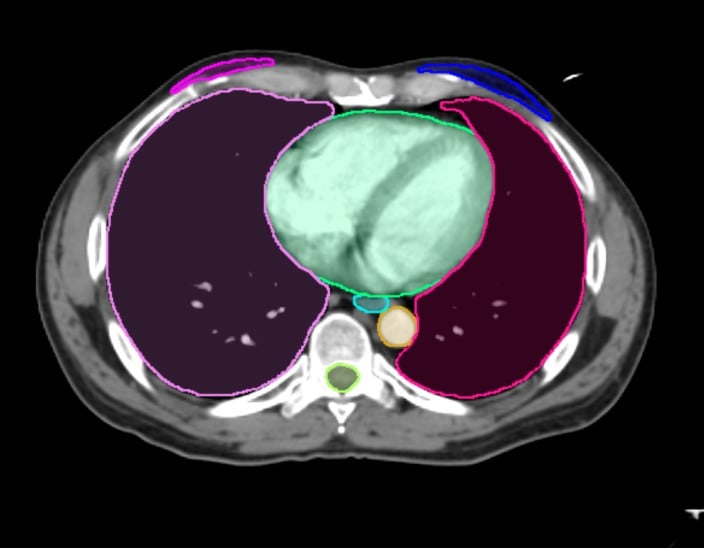

OAR Contours

Available Structures for Organ Contouring

Thorax CT

- BrachialPlex_L

- BrachialPlex_R

- New! Breast_L_RTOG

- New! Breast_R_RTOG

- Breast_L

- Breast_R

- Bronchus

- Carina

- Cricoid

- Esophagus

- Glnd_Thyroid

- GreatVes

- Heart

- Humerus_Head_L

- Humerus_Head_R

- Kidney_L

- Kidney_R

- Larynx

- Liver

- New! LN_Ax_L1_L

- New! LN_Ax_L1_R

- New! LN_Ax_L2_L

- New! LN_Ax_L2_R

- New! LN_Ax_L3_L

- New! LN_Ax_L3_R

- New! LN_IMN_L

- New! LN_IMN_R

- New! LN_Sclav_L

- New! LN_Sclav_R

- Lung_L

- Lung_R

- Musc_Constrict

- Pancreas

- SpinalCord

- Stomach

- Trachea